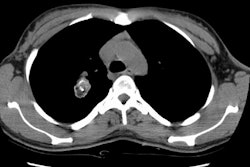

obstructive pneumonia. Bronchial carcinoids radiologically manifest as hilar or

perihilar masses, with or without associated atelectasis, pneumonia,

bronchiectasis, or mucoid impaction. At computed tomography, an anatomic

relationship of these tumors to a bronchus is usually seen, and they may show

contrast material enhancement or calcification. In rare cases, carcinoids occur